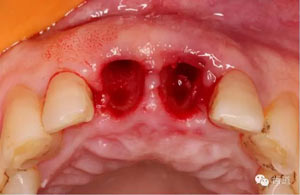

微創(chuàng)拔除根折牙

拔牙窩

探查唇側(cè)骨板(約齦下3-4mm)